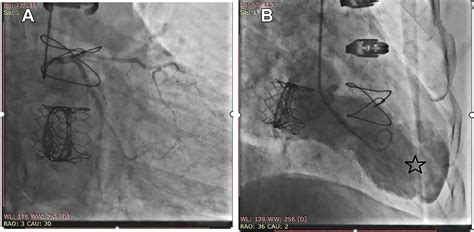

• Surgical Intervention: In severe cases, surgery may be necessary to repair or remove the aneurysm. This can involve:

Ventricular Aneurysmectomy: This procedure involves surgically removing the aneurysm and reconstructing the ventricle.

Coronary Artery Bypass Grafting (CABG): This surgery reroutes blood flow around blocked arteries to improve blood supply to the heart.

• Minimally Invasive Procedures: Exploring less invasive surgical options to repair aneurysms and reduce recovery time.